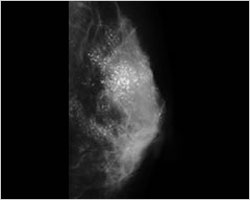

図1 若年者のマンモグラフィ